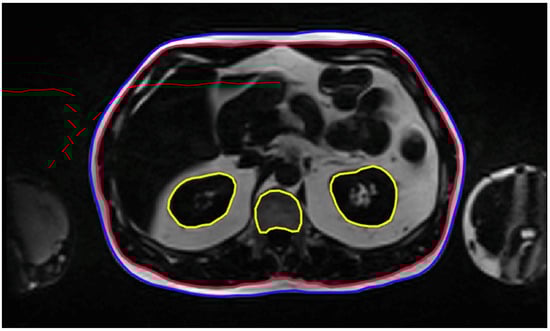

2.4. Volumetric and Metabolic Quantification of Adipose Tissue